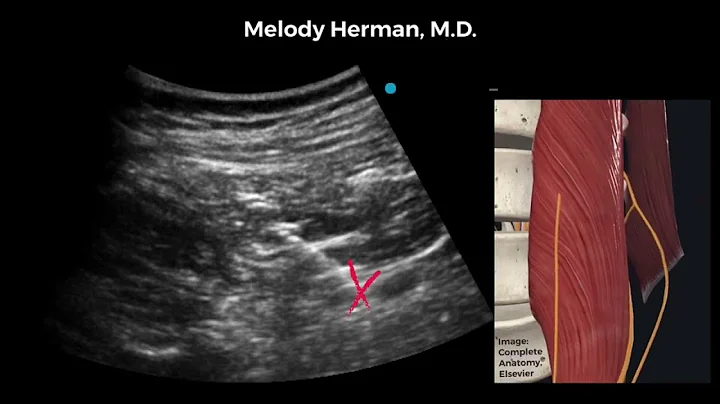

In this video we discuss the anterior approach to the quadratus lumborum block (also known as QL3, or the transmuscular